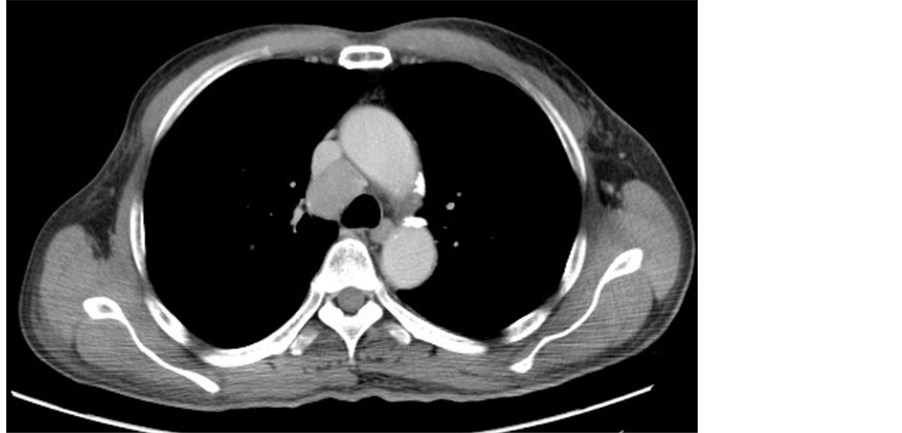

A 61-year-old man with dermatomyositis was referred to our hospital because of mediastinal lymph node adenopathy that had been detected by computed tomography (CT). The CT scan revealed a round, 3-cm-diameter mass in the upper mediastinum (Figure 1). Whole-body positron emission tomography/CT revealed abnormal accumulation of substrate within the mediastinal tumor and greater curvature of the stomach (Figure 2).

Figure 1. Computed tomography scan showing mediastinal lymph node adenopathy.